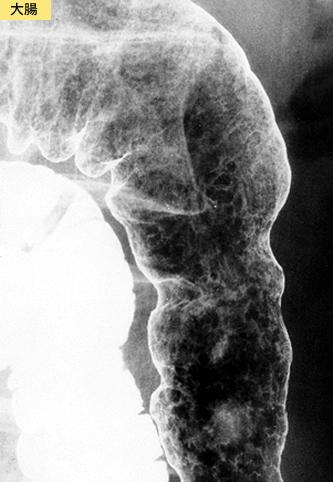

疾患(病理主体)の分類炎症性・潰瘍性疾患/消化管アミロイドーシス

部位(臓器別)大腸/横行

検査方法X-P